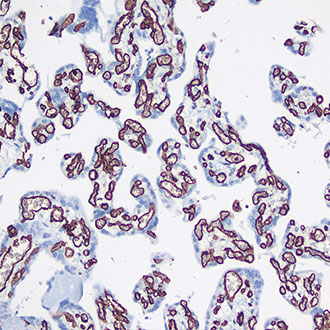

IHC

免疫组织化学(IHC)